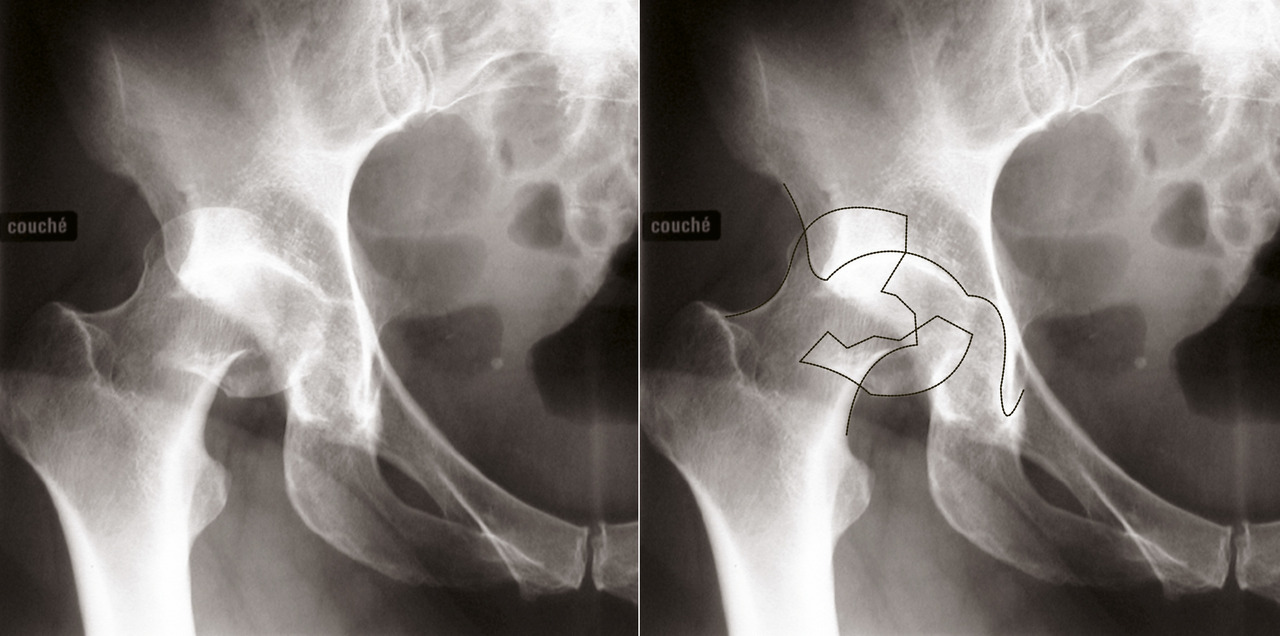

La luxation (fig. 17) : c’est la complication la plus fréquente des arthroplasties, qui peut survenir malgré l’utilisation de système de prothèses plutôt stables, souvent liée à la mauvaise observance des patients vis-à-vis des gestes à éviter. Cela peut aussi être le signe d’une infection sous-jacente, qu’il faudra alors rechercher par la réalisation d’une ponction articulaire au moment de la réduction de la luxation au bloc opératoire.